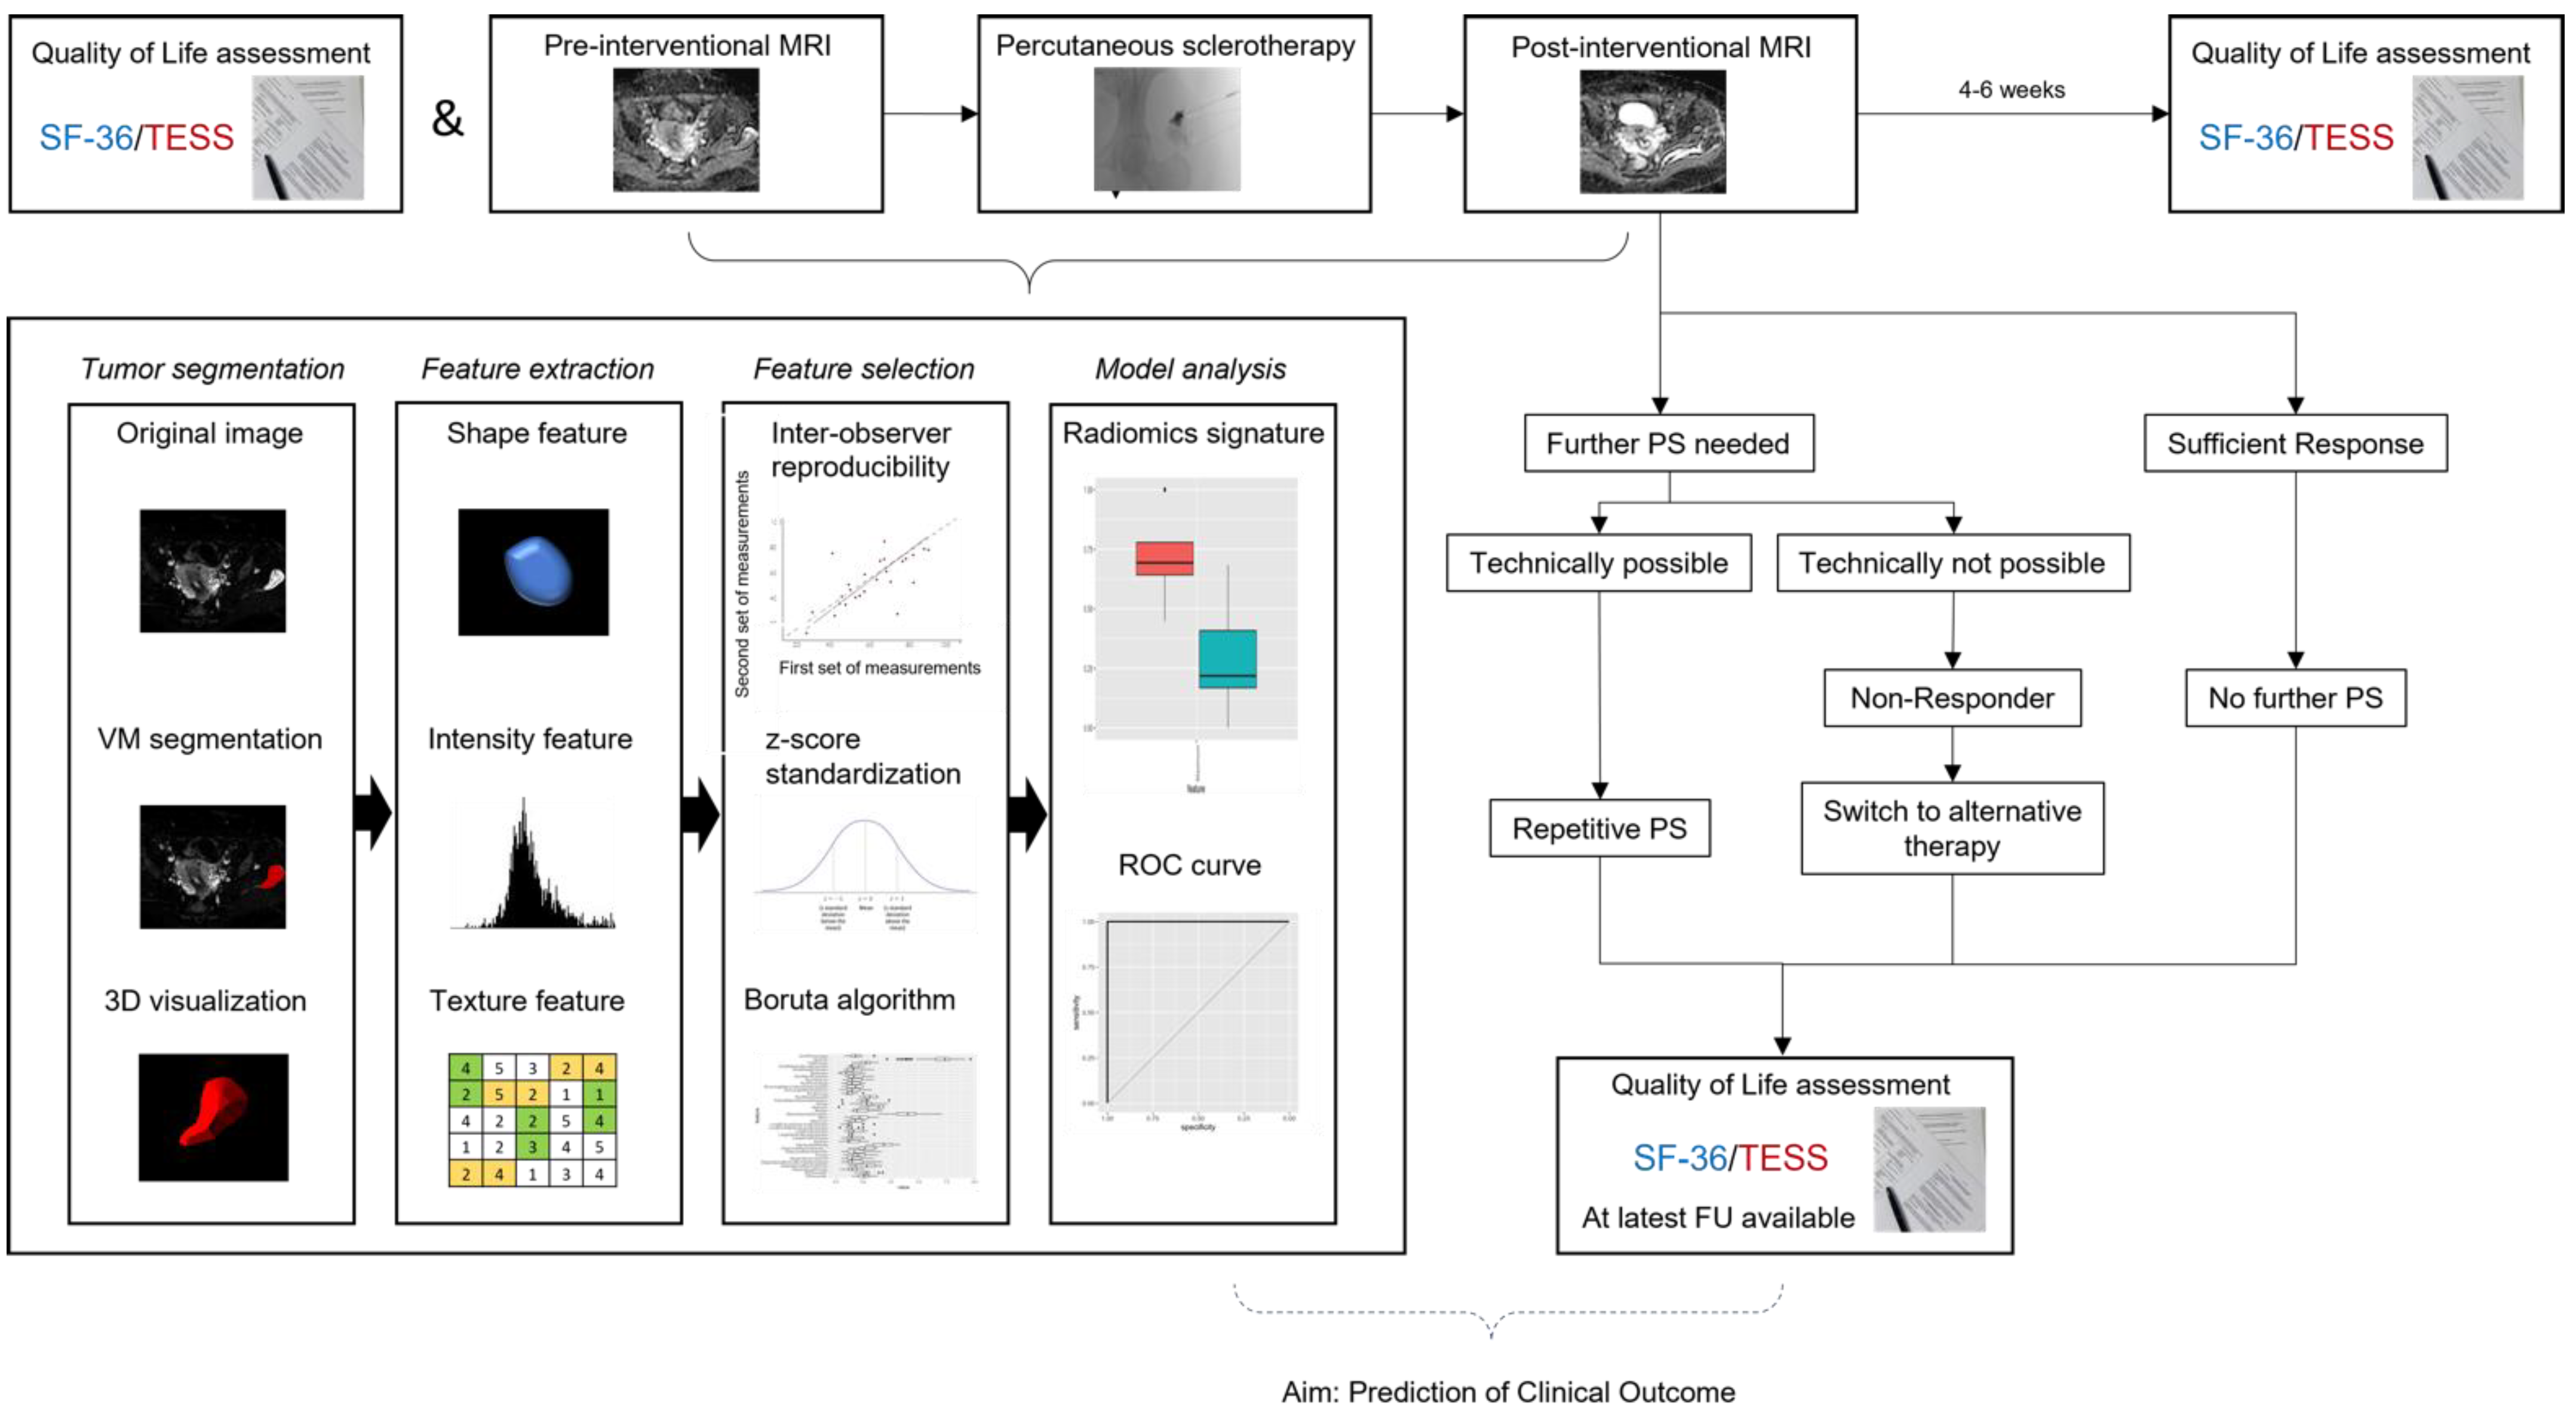

2.1. Study Design

2.5. Image Analysis and Radiomic Feature Extraction

2.6. Radiomic Feature Selection and Dimension Reduction for Differentiation of Response to Interventional Therapy

2.7. Statistical Analysis